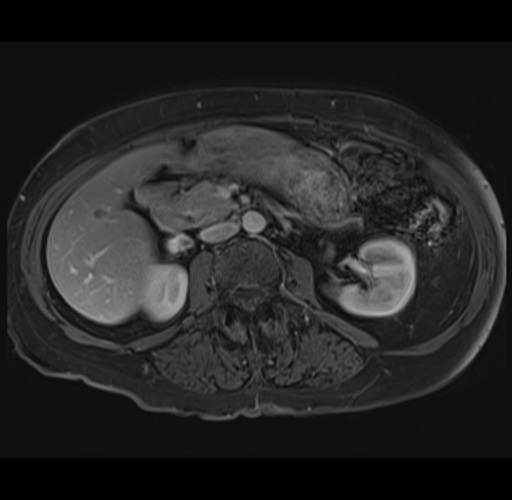

MRI T1